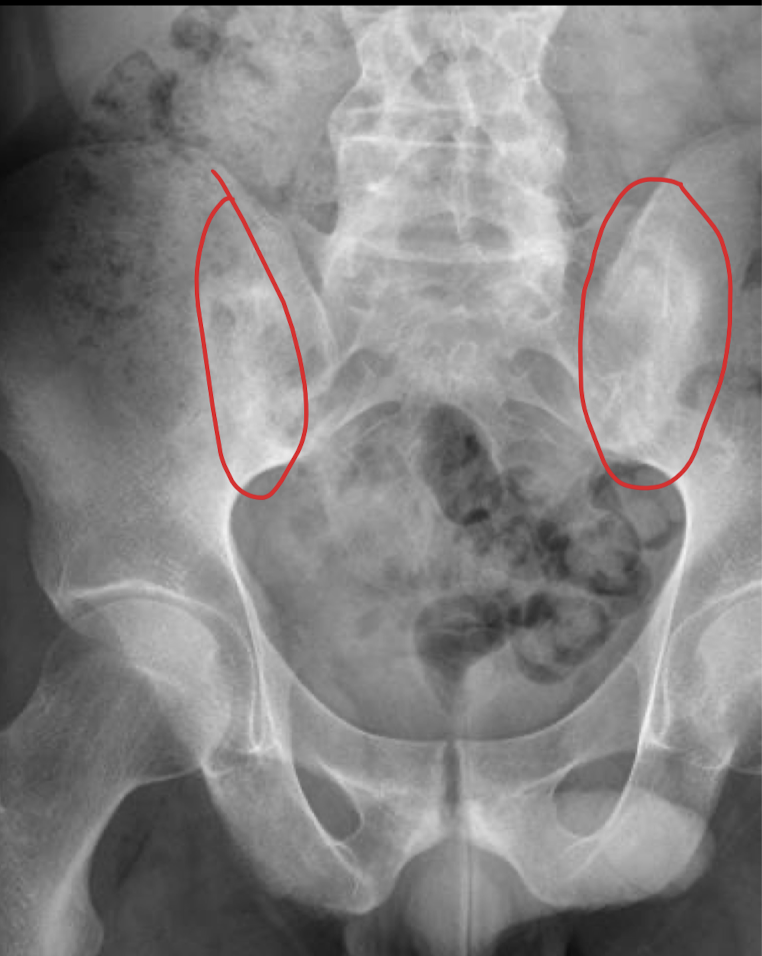

RX

A

POCA SENSIBILIDAD

util en crónico

esclerosis sacroiliaca: radioopacidad

irregularidad y ensanchamiento

TC: mismo